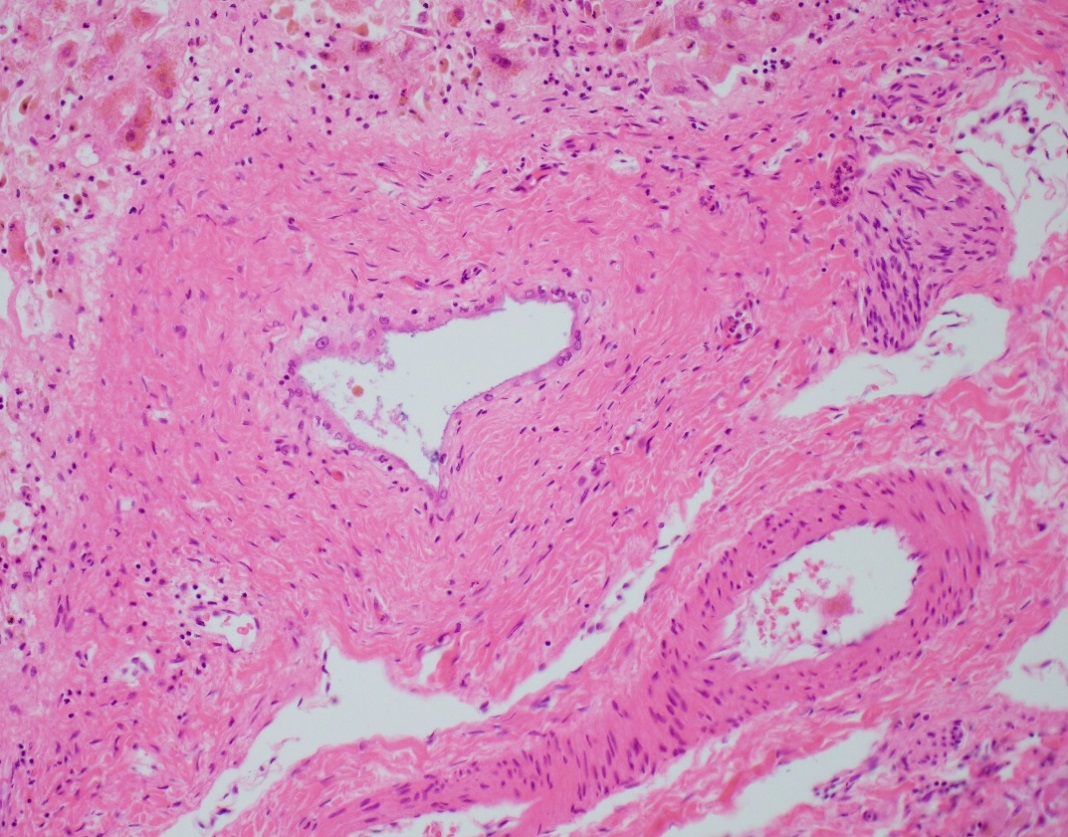

The explant showed submassive hepatocellular necrosis with marked cholestasis, and markedly dystrophic changes in bile duct epithelium in the portal tracts, but there was no ductopenia. Ductular reaction was conspicuously absent. The portal tracts showed mild chronic inflammatory infiltrate, associated with mild focal endothelialitis, and reduced number of small arterial branches. Medium-sized bile ducts showed periductal fibrosis along with dystrophic epithelial changes. Large bile ducts showed foci of intraepithelial lymphocytes, and focal reactive changes. There was central perivenulitis, with foci of lobular microabscesses. There was no foam cell arterial lesion, fibro-muscular intimal thickening, or inflammatory infiltration of muscular arteries. Trichrome stain highlighted fine perisinusoidal fibrosis, extending to portal tracts, but there is no bridging fibrosis. Reticulin showed a largely preserved architecture. A cytomegalovirus immunostain was negative.

Histologic features of chronic rejection and ischemia.

With the abnormal imaging and operative finding of the small caliber of proximal hepatic artery, and due to histologic overlap with CR, a component of ischemic cholangiopathy could not be entirely excluded.